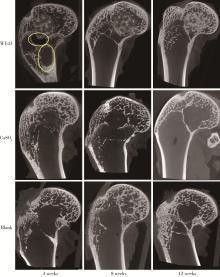

Figure 4

Comparison of lateral femoral condyle radiographs at different time points, the yellow oval indicates gas production"